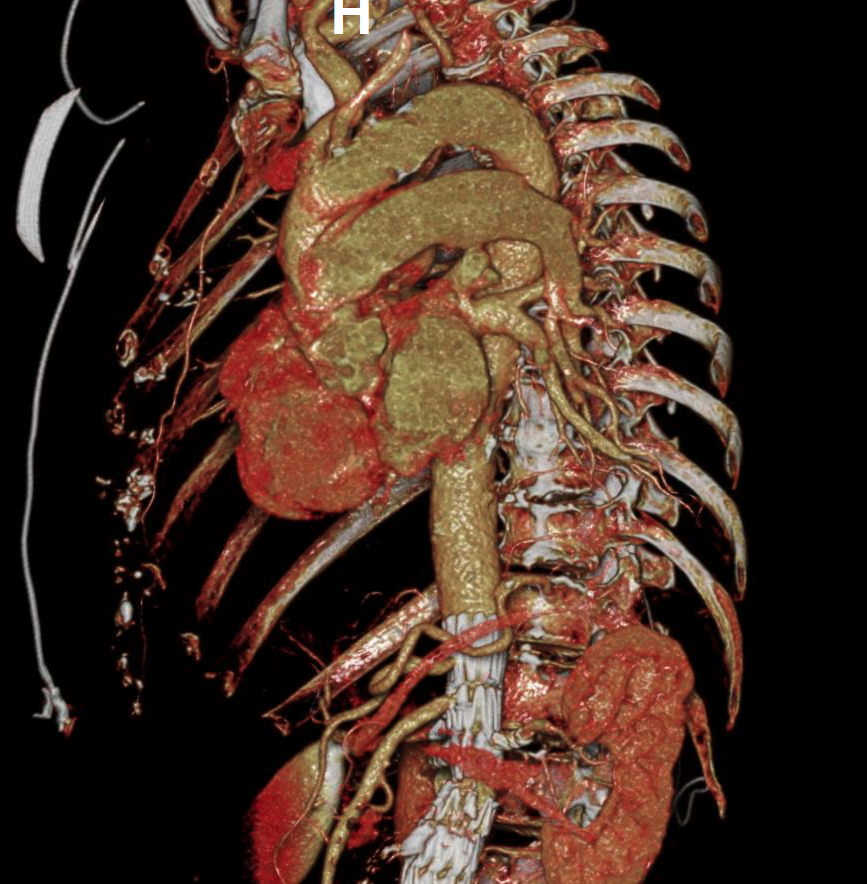

Our Post-Stent Service provides imaging for patients with stent placements in the abdominal aorta and common iliac arteries. The primary goal is to monitor changes in the maximum diameter of these vessels, ensuring early detection and management of post-stent issues. Using 3D imaging techniques identify critical aspects such as stent length, potential migration, and aortic diameter.

This protocol complements Routine Chest, Abdomen, and Pelvis imaging, offering an added layer of post-procedural monitoring. It allows quick viewing of major anatomy and focuses on identifying stent movement or aneurysm growth, ensuring comprehensive and effective monitoring.

Our 3D Printing Service provides anatomical 3D printed models for surgical planning and education. 3D prints can be requested during the 3D imaging ordering process. To achieve optimal results we require high-resolution CT or MRI scans. Once the scan is obtained, we begin the process by segmenting the medical images to isolate specific anatomical structures. This segmented data is then converted into a 3D model and reviewed by the requestor.

Final models are produced using advanced 3D printing technologies such as Fused Deposition Modeling (FDM), Stereolithography (SLA), and PolyJet. We offer hand delivery for on-site requestors and mail delivery for those at other Stanford locations. Additionally, we are exploring the development of custom cutting guides to assist in surgical procedures.